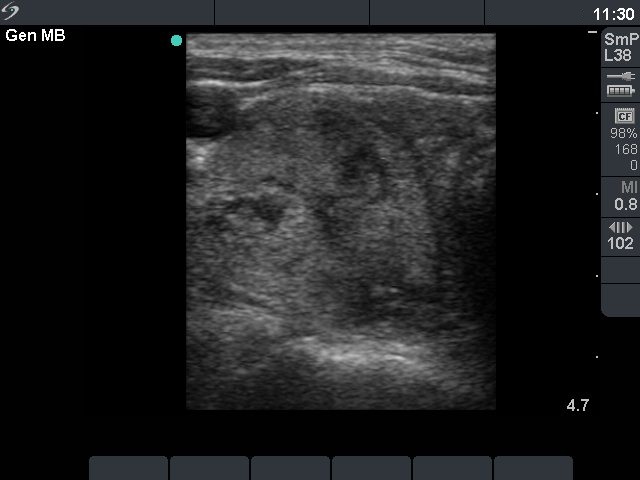

Ultrasonography: The thyroid was moderately hypoechogenic and showed increased vascularity. There was an echonormal nodule in the right lobe with combined perinodular and intranodular vascular pattern.